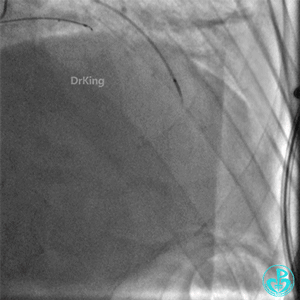

右冠脉支架通畅无狭窄,右冠脉给前降支远端提供逆向侧支循环。

EBU指引导管左冠脉造影显示粗大前降支中段闭塞,闭塞段近端有对角支发出,前降支同侧逆向显影,闭塞段不长。